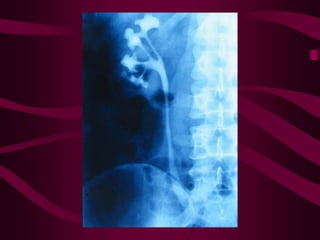

Este documento describe la tuberculosis genitourinaria. Afecta más a hombres que a mujeres. Se transmite principalmente a través de la infección pulmonar primaria y luego se disemina a través de la sangre a los riñones u otros órganos. Causa lesiones como granulomas y necrosis si no se controla, lo que puede provocar complicaciones como abscesos e insuficiencia renal. Se diagnostica mediante pruebas de orina y tratamiento con medicamentos durante varios meses.